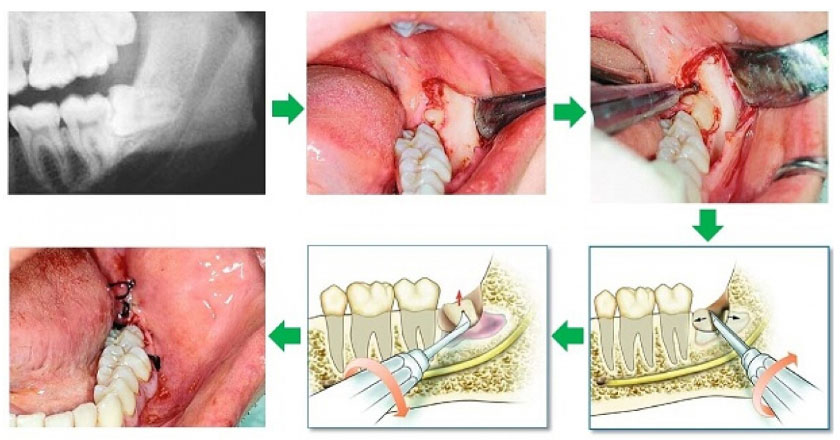

Một ca nhổ răng khôn tại Nha khoa Thục Toàn

Kết quả và phương pháp có thể thay đổi tùy theo thể trạng mỗi người

Quy trình nhổ răng bằng máy Piezotome tại Nha khoa Thục Toàn: https://nhakhoathuctoan.com/nho-rang-khon-va-quy-trinh-nho-rang-khon-moc-lech/

MỘT SỐ CASE NHỔ RĂNG BẰNG MÁY SIÊU ÂM PIEZOTOME

TẠI NHA KHOA THỤC TOÀN